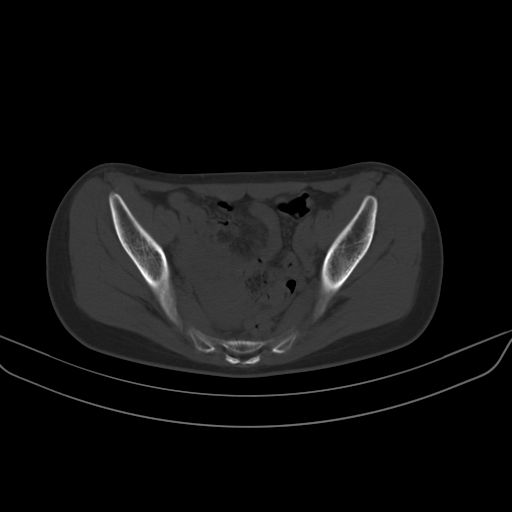

以下是引用zsl6918在2008-7-11 21:40:00的发言:[br]双侧骶髂关节骨质破坏以下三分之一为主,符合强直性脊柱炎表现

以下是引用zhangzhongshou在2008-7-11 21:41:00的发言:[br]患者是女性,hla-b27抗原(—),首先不太考虑强直性脊柱炎,建议查类风湿因子,骶髂关节改变考虑类风湿性关节炎可能性大,建议进一步检查。